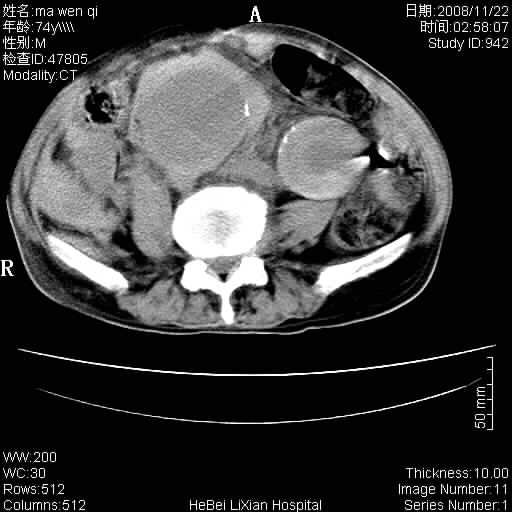

患者男 74岁.突然昏迷,休克6小时.血压70/30,头颅ct未见异常,既往体健.

补充病史,保留导尿10小时,尿袋内只有少许尿液,患者于住院后15小时后去世.

腹主动脉、双侧髂动脉夹层动脉瘤破裂出血进入腹腔。

1)考虑双侧髂动脉瘤并右侧动脉瘤破裂出血,右侧腹膜后及腹腔积血。2)双侧腹股沟疝。

1)考虑,腹主动脉、双侧髂动脉夹层动脉瘤破裂伴右侧腹膜后及腹腔积血。2)双侧腹股沟疝。